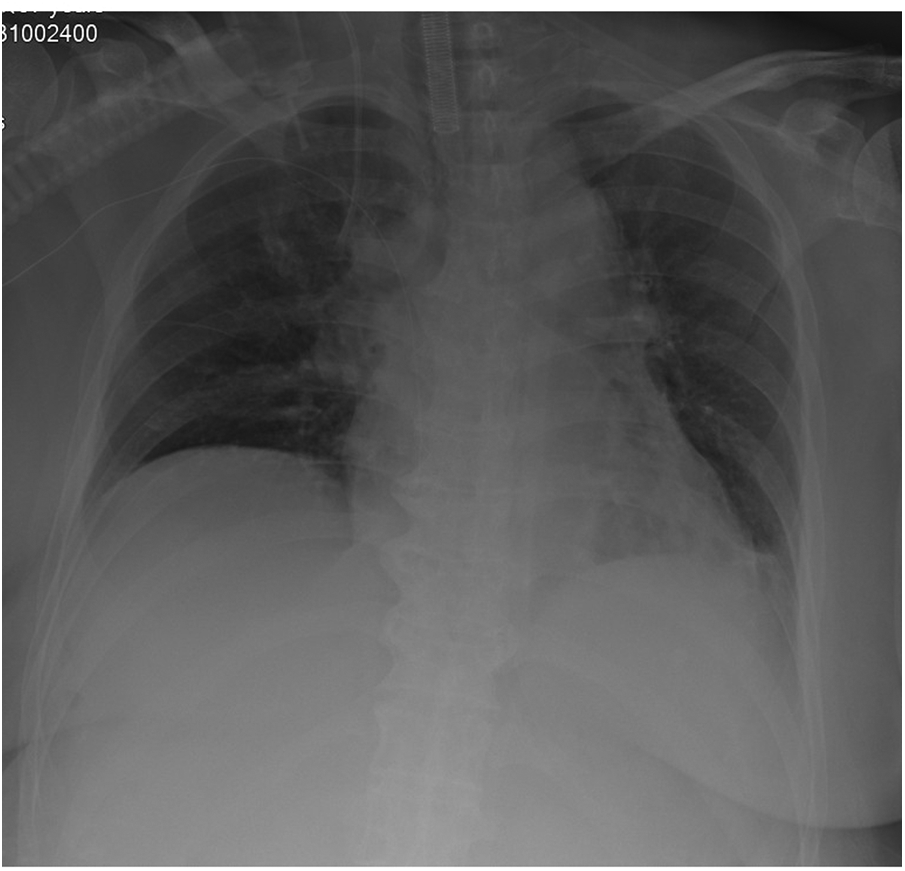

In the whole period of surgery, the hemodynamic was maintained by noradrenaline when needed. IBP and HR were controlled at 90–110/40–50 mmHg and 60–75 beats/minute. CI and SVV were maintained at 1.9–2.6 L/min.m2and 5–16. Lac was decreased from 0.9 mmol/L at the beginning to 0.6 mmol/L at the end of the surgery. Hb was decreased from 9.6 g/dl at the beginning to 8.5 g/dl at the end of the surgery.The patient was transferred to intensive care unit (ICU) after the operation. x-Ray of Chest revealed the elevated diaphragm was descended at a normal position (Figure 4). Patient underwent five separate sessions of intraperitoneal thermoperfusion chemotherapy from the 3rd to the 8th day after surgery; She had her abdominal drain removed on the 11th postoperative day, and was discharged on the 15th postoperative day. No other complications were observed.

Figure 4

Chest x-ray revealed a normal position of diaphragm.